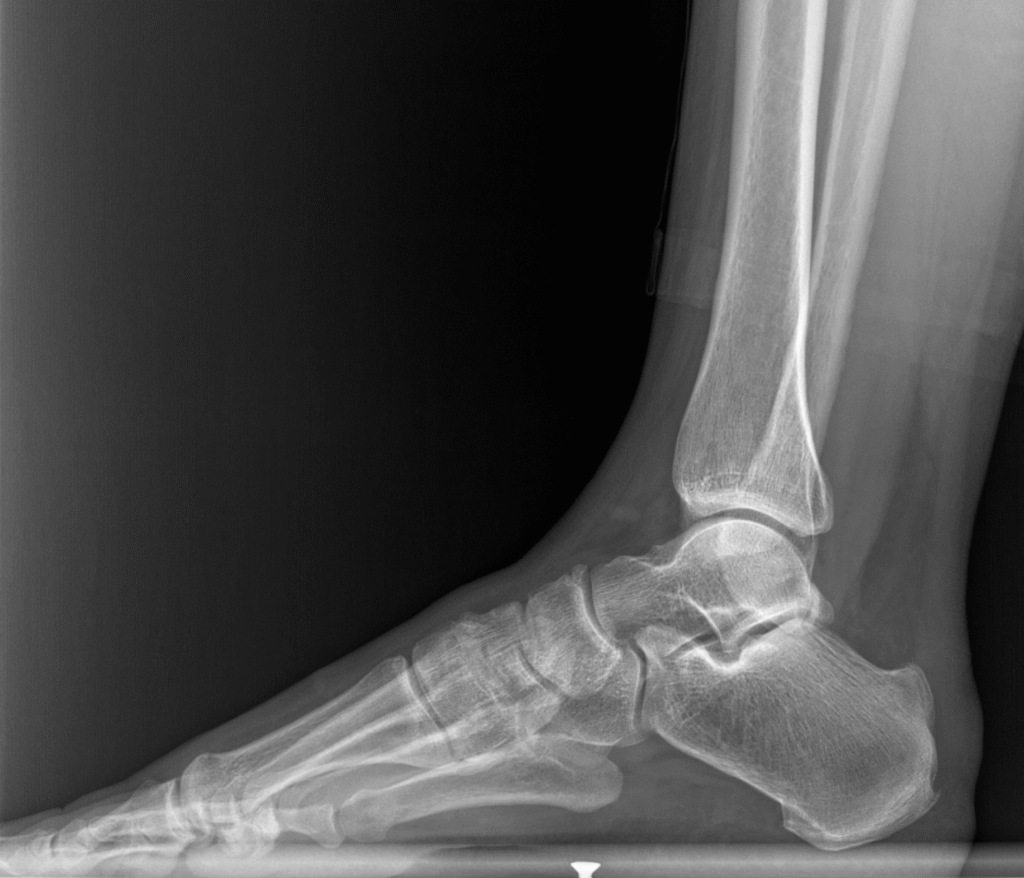

- Röntgen (Basarak grafi): Topuk kemiğinde Haglund deformitesi izlendi.

Preoperatif MRG ve röntgenler